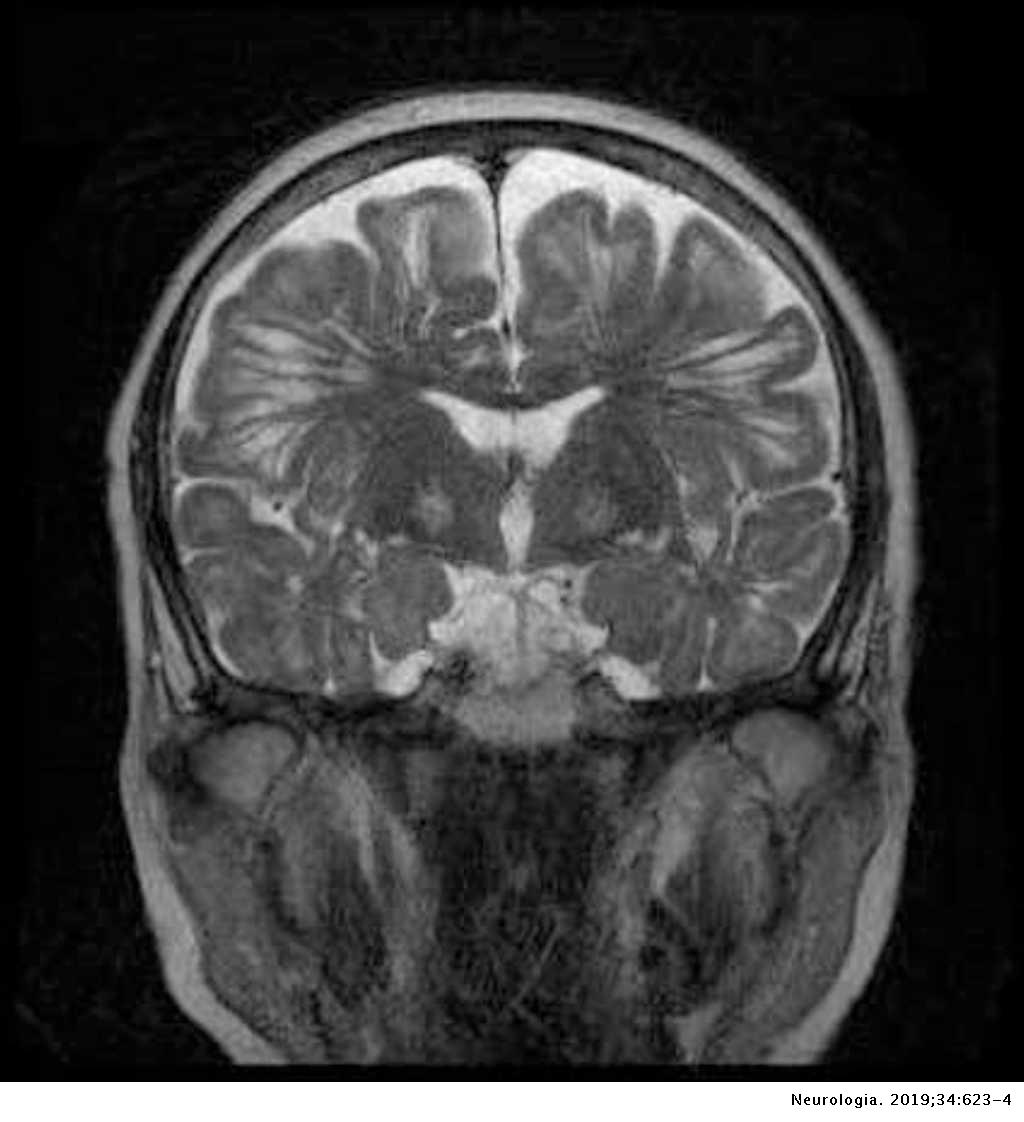

Lista muestra hermosas imágenes de resonancia magnética cerebral normal y anormal dinosenglish.edu.vn para que puedas explorar más en detalle.

resonancia magnética cerebral normal y anormal Pin en NEUROCIENCIAS resonancia magnética de cerebro Resonancia magnética (RM) de cerebro, corte axial ponderado en T2: la … VIDEO Nueva mancha en la Resonancia

Engineer Team : RESONANCIA MAGNETICA Magnetic Resonance Imaging – Clinical Images Hallazgos por resonancia magnética cerebral de nuestro paciente. M, 21 … Imágenes por resonancia magnética anormales como predictoras de mal … Imágenes por resonancia magnética anormales como predictoras de mal … Lesiones en resonancia magnética (RM) del encéfalo y la médula espinal … Pin en Resonancia Magnética del Encéfalo A) Resonancia magnética cerebral (RMC) mostrando infartos en … Caso 1: Edema cerebral visualizado mediante RM. (A) Secuencia T1 plano … Rascacielos dormir pasta tac y resonancia diferencias retrasar … Pin on Apuntes de Enfermería y T.C.A.E Resonancia magnética cerebral secuencia T2, que muestra lesión … Meningitis aguda en la enfermedad de Behçet | Reumatología Clínica Resonancia magnética coronal normal del cerebro Fotografía de stock – Alamy Imágenes de resonancia magnética, la imagen de la cabeza en diferentes … Resonancia magnética cerebral A) protocolo T1 sagital (Caso 1). Se … Resonancia magnética cerebral. Secuencia T1 corte sagital. Atrofia … Resonancia magnética de cerebro, cortes axiales, secuencias T2. Señal … Resonancia magnética de cráneo. A y B) Cortes axiales FLAIR … Resonancia magnética (RM) de cerebro, corte axial ponderado en T2: la … RM cerebral: Interpretación paso a paso | Kenhub Resonancia magnética de cerebro, cortes axiales, secuencias T2. Señal … De Resonancia Magnética De Cerebro Foto de archivo – Imagen de arteria … Top 107+ Imagenes de resonancia cerebral normal – Destinomexico.mx -Imagen por resonancia magnética del cerebro. a) Cortes sagital y axial … resonanCia magnétiCa Cerebral donde se observa hiperintensidad a nivel … MRI (Imagen de resonancia magnética) – Tomografía computarizada de la … Meningioma – NCI Imágenes por resonancia magnética coloreadas del cerebro sano del … Resonancia magnética cerebral en secuencia FLAIR, que muestra lesiones … Contraste resonancia magnetica cerebral – senturinthegreen Relación de los espacios de Virchow-Robin con la enfermedad de … Gliomatosis cerebral – Instituto Nacional del Cáncer Pin en Neurology. Recomendaciones para la utilización e interpretación de los estudios de … Fotografía De La Proyección De Imagen De Resonancia Magnética Del … atmósfera Dirigir Cumplir anatomia resonancia magnetica Desarrollar … Pin en #MEDICINA,#SALUD Resonancia magnética de la nasofaringe De Resonancia Magnética De Cerebro Foto de archivo – Imagen de polilla … Atrofia cortical global de predominio parietal en la Resonancia … Resonancia magnética cerebral | Download Scientific Diagram Neuroblog: Resonancia magnética cerebral en la trombosis crónica de … De Resonancia Magnética De Cerebro Imagen de archivo – Imagen de … ¿Cuáles son los riesgos de la resonancia magnética? – Integra Salud … Resonancia magnética cerebral al decimocuarto día de ingreso: área … Resonancia magnética. Corte axial mostrando área infartada en el … Resonancia magnética cerebral del paciente AV evidenciando lesiones en … -Ressonância magnética de encéfalo mostrando múltiplas imagens … Resonancia magnética cerebral secuencia FLAIR (Fluid Attenuated … Resonancia magnética cerebral con protocolo de epilepsia, en sección … Resonancia magnética cerebral en corte sagital. Se observa una evidente … Resonancia magnética craneal en la que se evidencian lesiones … Logran visualizar el cerebro a detalle más completo tras una resonancia … Así decide el cerebro la severidad de un castigo De Resonancia Magnética De Cerebro, Imagen de archivo – Imagen de … A) Resonancia magnética cerebral; Secuencia Tof: oclusión de arteria … Un estudio asocia la ansiedad con la aparición rápida del Alzheimer IMÁGENES DE 18 F-PR04.MZ PET FUSIONADA CON RESONANCIA MAGNÉTICA … Imágenes por resonancia magnética anormales como predictoras de mal … Tumores de la región pineal – Instituto Nacional del Cáncer Epilepsia: una historia de voces y fantasmas | Neurología Contribución de las imágenes de resonancia magnética por tensor de … Resonancia magnética secuencia T2 plano coronal de quiste epidermoide … Resonancia Magnética Cerebral del paciente: a. Aumento de… | Download … Resonancia magnética cerebral 2022 Síndrome de hemiconvulsión-hemiplejía-epilepsia. Seguimiento de un caso … Enfoque Radiologico: La resonancia magnética permite detectar lesiones … Resonancia magnética craneal T1 con contraste que muestra angiomatosis … guidewiz – Blog Resonancia magnética cerebral, secuencia SWI. Ribete hipointenso en la … resonAnCiA mAgnétiCA de ColumnA Con gAdolinio. Corte sAgitAl en t1 de … SEMANA 12: FUNDAMENTOS DE RESONANCIA MAGNÉTICA NUCLEAR. INDICACIONES Y … DIAGNÓSTICO DE ESCLEROSIS MÚLTIP Magnetic resonance imaging of the brain – Alchetron, the free social … Resonancia magnética de órbitas | Instituto Radiológico Dr. E Castillo Alteración de la marcha en un paciente post-trasplante hepático Resonancia magnética cerebral de un paciente sano (Ay B) y paciente que … Utilidad de la resonancia magnética craneal para el diagnóstico de la … Resonancia Magnética Del Cerebro El Tumor Cerebral Foto de stock y más … De Resonancia Magnética De Cerebro Imagen de archivo – Imagen de … ABDALLA RADIOLOGIA: NEURINOMA ACUSTICO Atrofia cortical global de predominio parietal en la Resonancia … Resonancia Magnética : Producción de la imagen MRI Brain Scan — Stock Photo © Bunyos30 #18724051 Mri (imagen de resonancia magnética) Monitor con imagen de captura de … Tomografía computarizada vs resonancia magnética: diferencia y … Tumores Cerebrales – Unidad de Neurocirugía RGS Resonancia magnética de la columna, sección sagital. Observe los discos … La resonancia magnética, una técnica imprescindible en el diagnóstico … Perfusión Cerebral por Resonancia Magnética | ¿Qué es? ¿Necesita Contraste? Resonancia Magnética Cerebro A: resonancia magnética, T2 coronal preoperatoria; se observa lesión en … Resonancia magnética cerebral — Foto de stock © Bunyos30 #27340623 La resonancia magnética se perfila como detector de mentiras | Futuro … Resonancia magnética cerebral en T1 con gadolinio, cortes axial (a … MRI brain : show brain tumor at right parietal lobe of cerebrum — Stock … NEUROIMÁGENES EN ENFERMEDAD DE PARKINSON: ROL DE LA RESONANCIA …